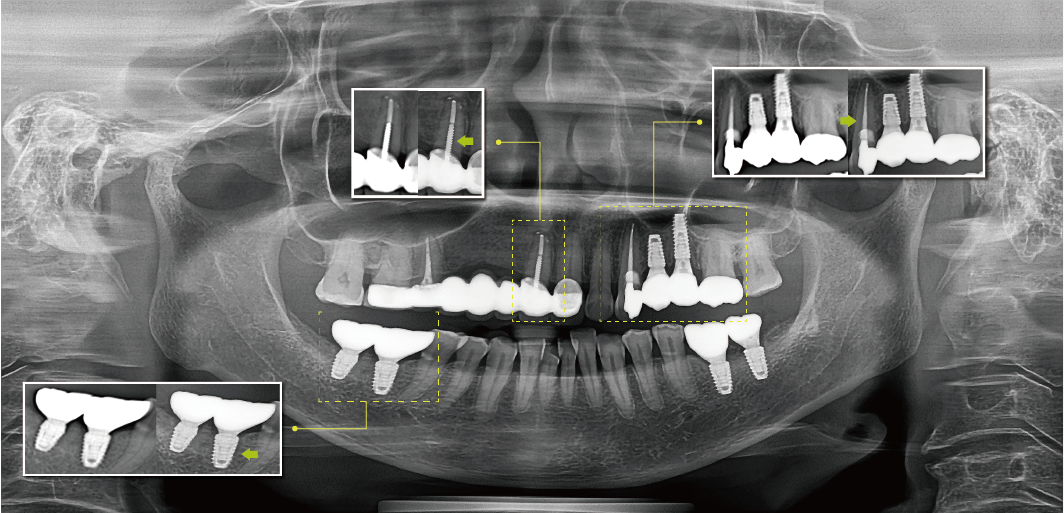

清晰的全景影像

通過多層技術,可以拍攝多張圖像,每張圖像被進一步分割。系統會自動選擇最佳焦點將其整合成一個優化的全景圖像。

前牙部畸變縮小,即使不單獨拍攝小牙片,也能準確診斷。清晰度可準確識別種植體螺紋和內部,確保連接程度和斷裂程度。